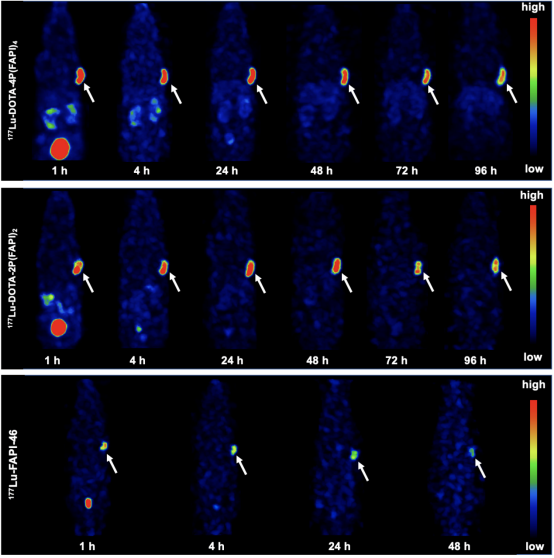

為了進一步評價該四聚體FAPI探針作為放射性治療藥物的可行性,利用診療一體化核素177Lu進行四聚體探針的放射性標記,并進行多時間點SPECT顯像,探索177Lu-DOTA-4P(FAPI)4在腫瘤中的攝取及體內(nèi)的分布特征。FAPI四聚體、二聚體和單體FAPI-46的代表性SPECT圖像如圖7所示。與64Cu-PET顯像結(jié)果相似,177Lu-DOTA-4P(FAPI)4HT-1080-FAP荷瘤鼠中的腫瘤攝取在各時間點顯著高于二聚體177Lu-DOTA-4P(FAPI)4和單體FAPI-46(7)生物分布實驗的定量結(jié)果(8)顯示:177Lu-DOTA-4P(FAPI)4在注射后24 h的腫瘤攝取為21.1.4±1.7% ID/g,腫瘤清除相對緩慢 (48h、72h96h分別為19.2±0.6% ID/g, 18.8±2.1% ID/g14.8±0.9% ID/g)。二聚體177Lu-DOTA-2P(FAPI)2在注射后24 h的腫瘤攝取為17.1±3.9% ID/g,略低于四聚體177Lu-DOTA-4P(FAPI)4,FAPI二聚體腫瘤中的洗脫速度FAPI四聚體快,在48、7296 h時的攝取值分別為18.8±4.1% ID/g、13.8±2.6% ID/g13.1±0.7% ID/g。單體177Lu-FAPI-46經(jīng)尾靜脈注射后24 h的腫瘤攝取顯著低于177Lu-DOTA-4P(FAPI)4  (3.4±0.7% ID/g, P<0.001)。

7. 177Lu標記FAPI四聚體、二聚體和單體在HT-1080-FAP荷瘤鼠模型SPECT顯像